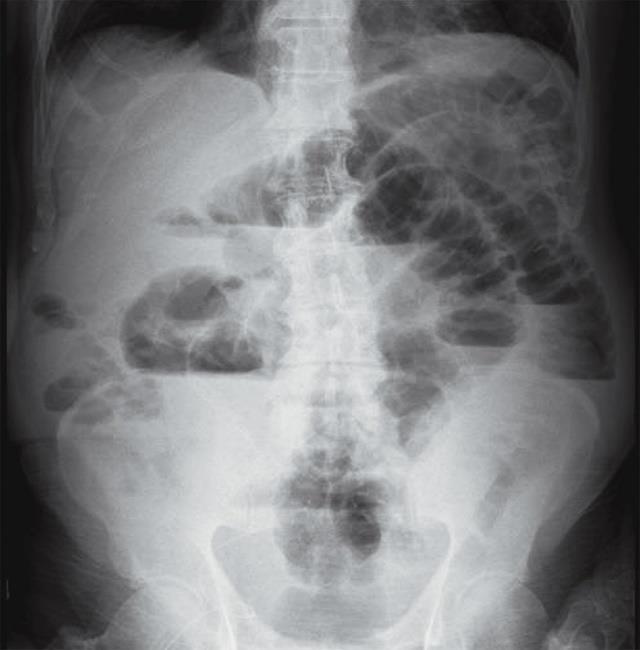

Setratadepacientemasculinode71años de edad originario de la Mixteca, Oaxaca, sin antecedentes patológicos de importancia, quien iniciamesesprevios,condificultadparaevacuar, distensión abdominal progresiva, así como dificultadparaexpulsargases,dichossíntomasse exacerban 72 horas antes previo a su internamiento, así mismo se acompaña de pérdidaponderalde6kilosaproximadamenteen los últimos 6 meses que no recibe tratamiento

médico, porloqueacudealserviciodeurgencias denuestraunidad,donderealizanunaradiografía deabdomen,dondesemuestrauncolondilatado, con engrosamiento de ileón distal, así como elevación de hemidiafragma izquierdo (Figura 1). A la exploración física se observa paciente pálido,caquéctico,conabdomendistendido ya laauscultaciónconhiperistaltismointestinal.La biometría hemática realizada muestra Hemoglobinade10g/dLyHematocritode32%, acompañadodeligeraLeucocitosis.Porloquees intervenido quirúrgicamente con diagnóstico presuntivo de Neoplasia intestinal. En la intervención quirúrgica se observa un colon dilatado, con válvula ileocecal prominente, con presencia de induración de ileón terminal (Figura2),elestudiohistopatológicomuestraun proceso ulcerativo profundo a nivel ileal, recubierto por restos celulares, células inflamatorias, fibrina y material hematoxilinico agrupadosengránulosdeaparienciafibrilar,que alteñirsecontécnicahistológicadePASdichos gránulos están constituidos por estructuras

1.

Radiografíaabdomen.Distensióndeasasintestinalesconniveleshidroaéreos.

Figura

La TAC (Tomografía axial computarizada) es el estudio radiológico de más utilidad. La enfermedad aparece como una masa de patrón sólido o quístico con una pared engrosada que capta contraste, generalmentesetratadeunamasadecarácter infiltrativo,extraointraluminal,acompañada de una llamativa reacción desmoplásticaque dificulta el diagnóstico diferencial con un proceso maligno. La punción percutánea dirigida por TAC puede tener fines diagnósticos y terapéuticos. Sin embargo, en algunos casos la radiografía simple de abdomensuelesereficaz.

caso de nuestra paciente los estudios de imagen y los hallazgos transquirúrgicos normaron una conducta ante un posible cuadro oncológico que no se confirmó en los estudios de patología. Se deben tomar estrategias para en lo subsecuente considerar procesos infecciosos versus procesos oncológicos en todos los pacientes con masa intestinal acompañada de datos de obstrucción, aunque la literatura marca el estudio tomográfico como el estudio de gabinete de mayor utilidad, en ocasiones por la severidad del cuadro clínico y al considerarse una urgencia quirúrgica puede sernoconsideradosisecuentaconalgúnotro estudio de imagen que apoye el diagnóstico demasatumoralen estudio.